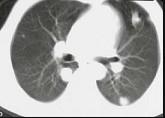

问题 男,40岁,化脓性胆管炎手术后3天出现高热,伴胸痛,咳嗽,CT如图,最可能的诊断为 ( )

选项 A.肺转移癌 B.金葡菌肺炎 C.肺淋巴瘤 D.肺多发性脓肿 E.肺组织胞浆菌病

答案 D